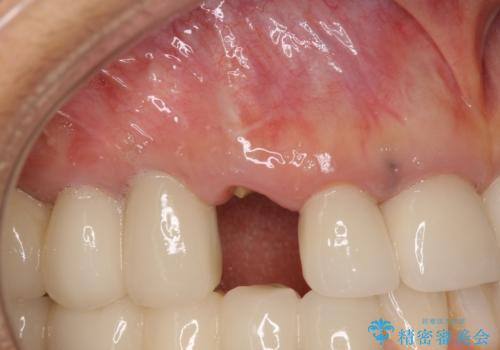

全顎的な治療後に、急遽ニューヨークへ転居されることとなったのですが、治療後から経過観察を行っていた右上犬歯が歯肉縁下に及ぶむし歯のため、クラウンが土台ごと外れてしまったとの連絡がありました。

他の部位にインプラント治療を行っていたことから、こちらの歯に対してもインプラントによる補綴治療を希望されたため、1泊での帰国時に抜歯、インプラント埋入、仮歯の装着を行い、数ヶ月後の帰国時にオールセラミッククラウンの型取りと装着を行う計画としました。